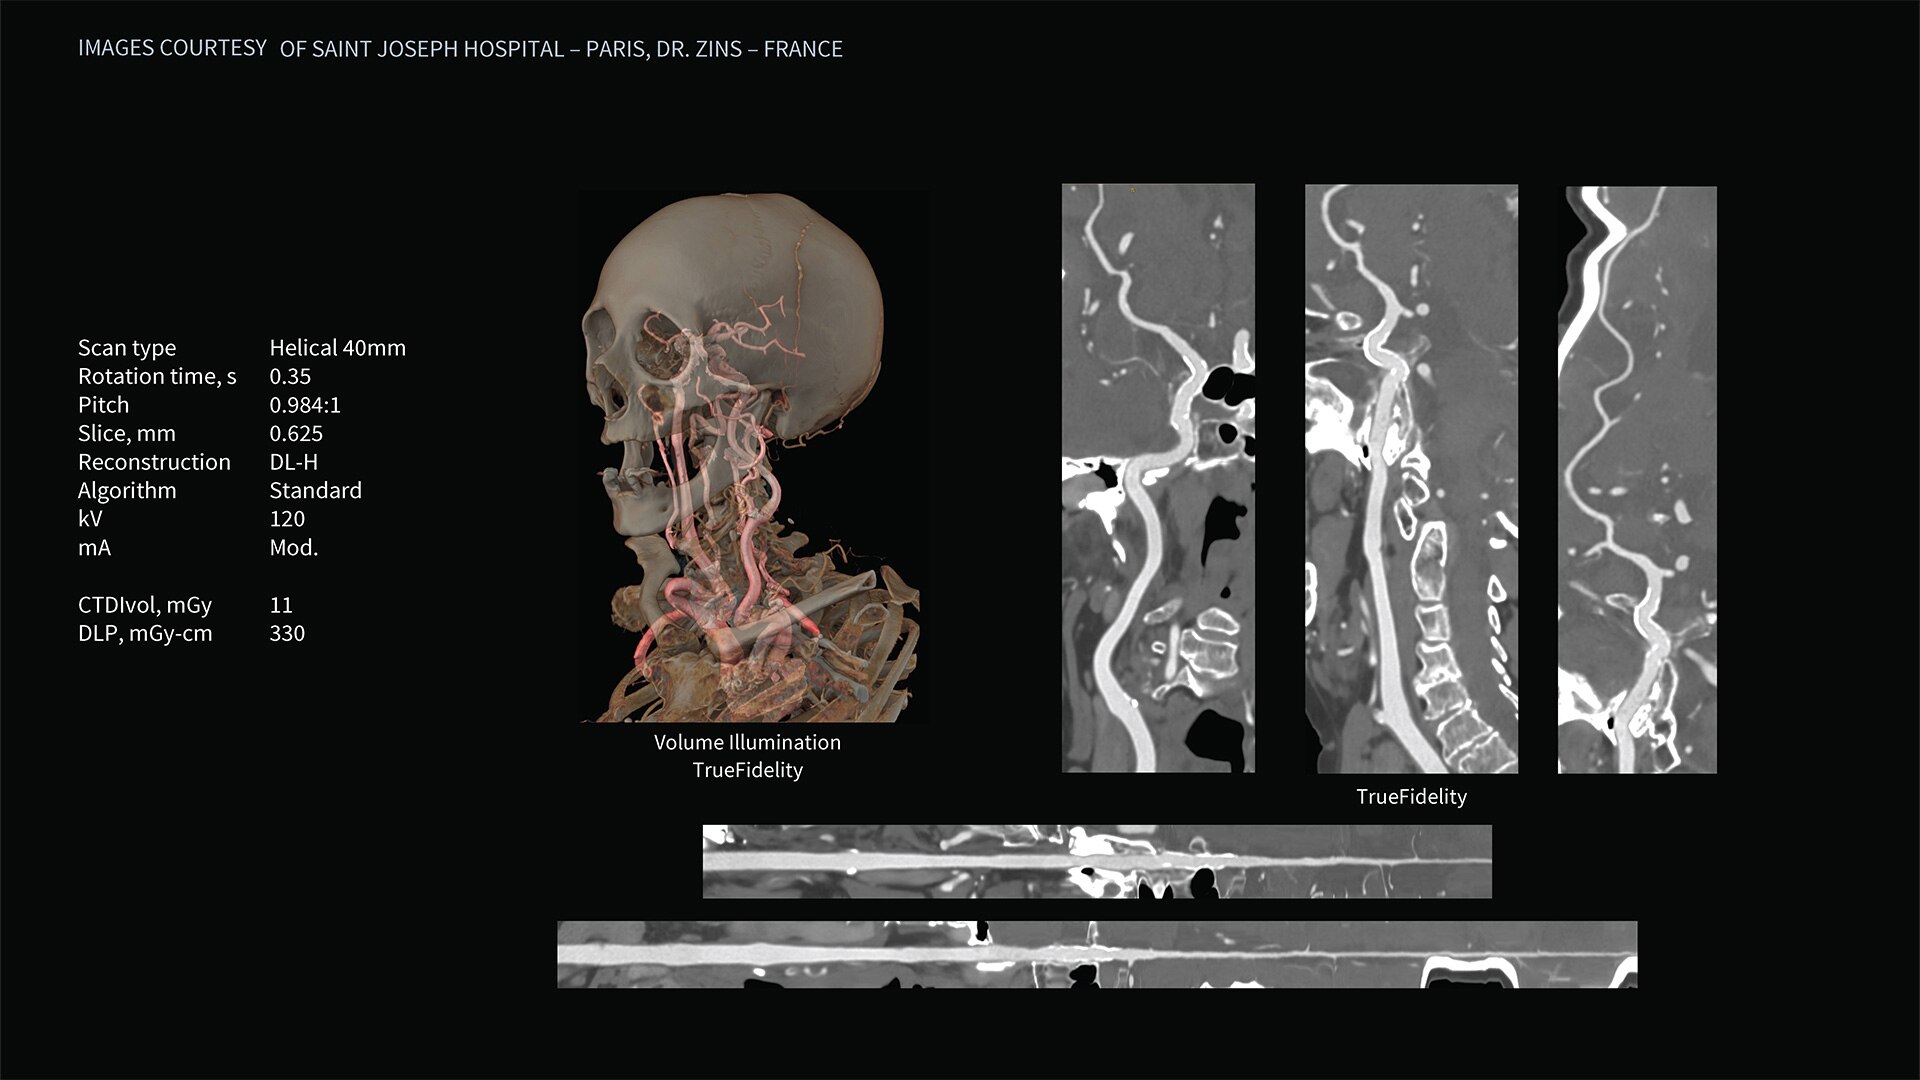

Deep learning image reconstruction, higher special resolution at 0.23 mm

Address individual clinical needs, moving seamlessly from one scan mode to the next. Image with a stunning 0.23 mm spatial resolution, then switch to rapid kV switching for full 50 cm FOV spectral imaging of the entire body. Choose up to six times reduction in motion artifact using SnapShot Freeze 2¹ for coronary artery CTA and reduce all-round dose with next-generation iterative reconstruction.